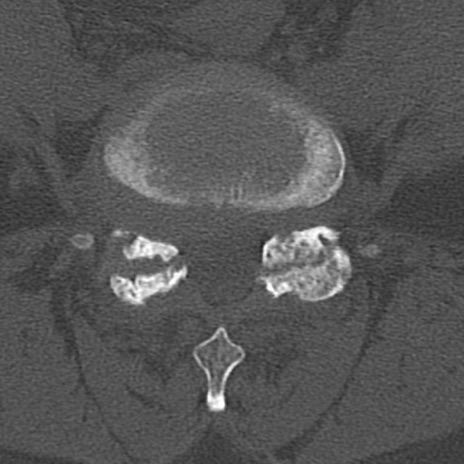

腰椎CT

横断像と矢状断像